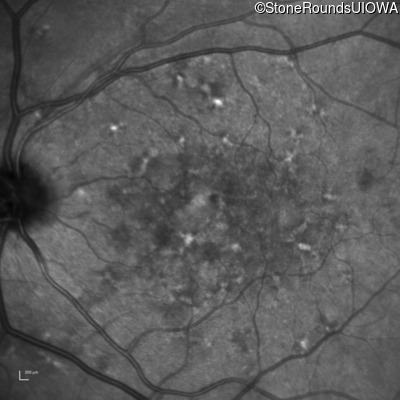

AR Stargardt Disease (IIA)

Age at visit: 59 years (Visit 3)

This 59 year old woman first noticed vision loss in her right eye a few months earlier. She has a cousin with Rhodopsin-associated RP.

Diagnosis & molecular findings

Disease Gene Allele 1 variant(s) Allele 2 variant(s) Inheritance mode

AR Stargardt Disease ABCA4 Arg219Thr AGA>ACA Gly863Ala (G)GA>(G)CA AR